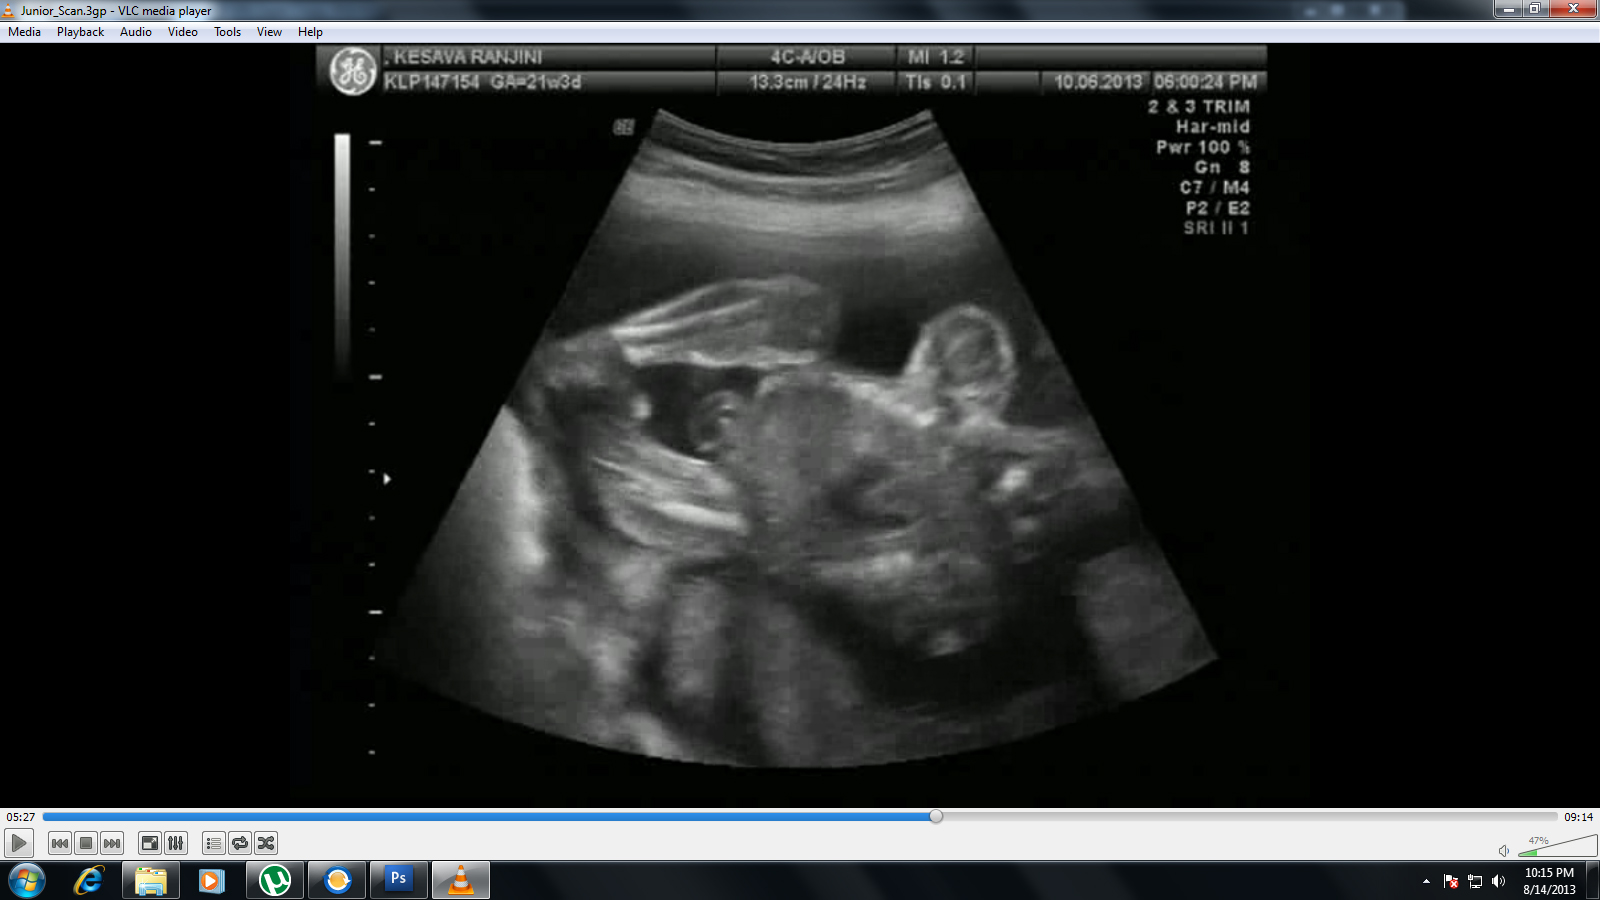

I've got my wife's ultrasound scan report of 21 weeks. Now she's 33 weeks. Attaching herewith the image. Someone please help.

Attachment 13155